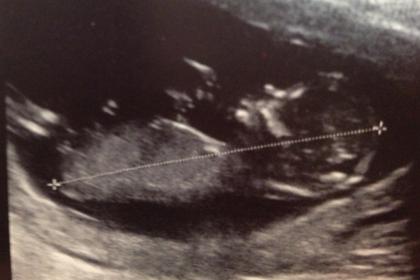

Attachment 7346

I thought i would add full piccie too.